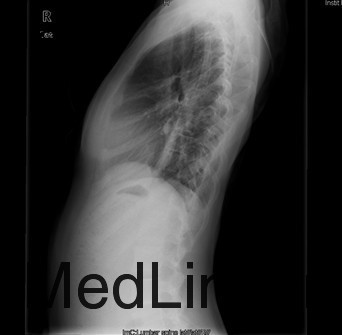

患者女,13岁,因“发现脊柱侧凸畸形4月”入院。患者4月前家长无意间发现胸背部脊柱侧凸,双肩不等高,无牛奶咖啡斑、无皮下结节,不伴活动耐力下降、气促、心悸、胸背痛、腰痛,日常活动及运动能力正常,在当地医院检查后建议手术治疗,到我院就诊,门诊以"特发性脊柱侧凸"收入住院。

查体:胸段脊柱向右侧凸,右侧胸廓后部凸起,剃刀背畸形,剃刀背高度2cm,右肩高,骨盆略向右倾斜,四肢及关节未见异常,未查见牛奶咖啡斑。脊柱各棘突及棘突旁无压痛及扣痛。胸腰部前屈、后伸及侧屈、侧旋范围正常,双下肢等长,未发现感觉减退区,四肢肌力5级,生理反射均正常引出,病理反射未引出。 辅查:X片示胸段脊柱以胸8为中心明显右侧弯畸形,胸段上段及腰段相应轻度左突侧弯。

初步诊断:特发性脊柱侧凸(Lenke:ⅡA ̄型) 诊疗计划: 拟经后路脊柱侧凸矫形+同种异体骨植骨+椎弓根螺钉内固定术术

术中见胸椎脊柱S形侧弯,肌肉韧性较差,棘突偏离中线,凹侧小关节退变明显,胸段脊柱以T8为中心明显右凸,T4为中心向左侧凸起,右侧剃刀背畸形。